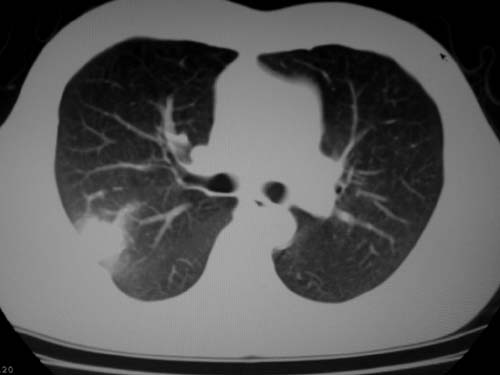

标题: CT19540: 31岁。自述结核性胸水治疗两个月后,在外院拍x线发 [打印本页]

标题: CT19540: 31岁。自述结核性胸水治疗两个月后,在外院拍x线发

右侧胸壁结节状软组织影伴相应肺叶内受侵,伴右侧胸腔积液。考虑:结核性可能大。

支持 右侧胸壁结节状软组织影伴相应肺叶内受侵,伴右侧胸腔积液。考虑:结核性可能大。

右侧胸壁结节状软组织影伴相应肺叶内受侵,伴右侧胸腔积液,结合临床,首先考虑结核。

1)考虑右侧结核性胸膜结节。2)右侧胸膜增厚+包裹性胸腔积液。